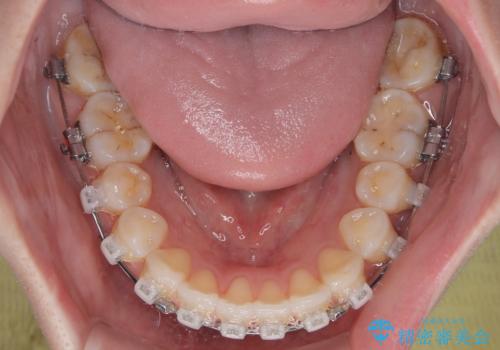

- クリアブラケット

舌の突出癖改善のためのトレーニングを指導しながら、ワイヤー装置にて矯正治療を行うこととしました。

舌のトレーニングは不十分でしたが、1年半ほどで治療を終えることができました。